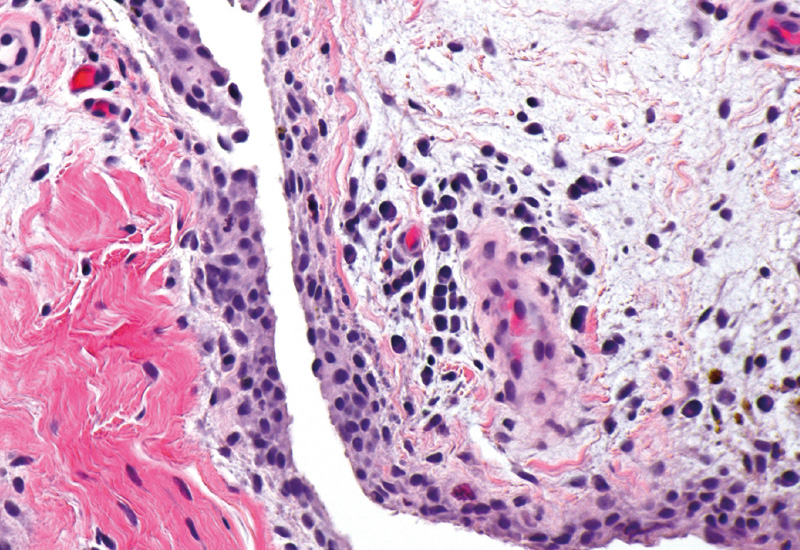

Bei der RA können demnach 6 CTAP unterschieden werden: Beim EFM-Typ überwiegen Endothelien, Fibroblasten und myeloische Zellen, beim F-Typ vor allem Fibroblasten. Der TF-Typ ist gekennzeichnet durch T-Zellen und Fibroblasten, beim TB-Typ dominieren T- und B-Zellen, beim TM-Typ T-Zellen und myeloische Zellen und beim M-Typ myeloische Zellen. Die Autoren weisen darauf hin, dass diese CTAPs mit Zytokinen, Risikogenen, Histologie und Serologie korreliert sein können, andererseits aber auch dynamisch sind und womöglich zur Prädiktion des Therapieansprechens genutzt werden könnten. So könnte die auf Basis dieser Studie vorgenommene Unterteilung dabei helfen zu erklären, warum verschiedene, an TNF, IL-6, B-Zellen oder am JAK-STAT-Signalweg ansetzenden Therapieprinzipien oder auch die T-Zell-Kostimulation bei einigen Patienten wirken, bei anderen aber nicht. Ob dies künftig tatsächlich gelingt, bleibt aber noch abzuwarten.